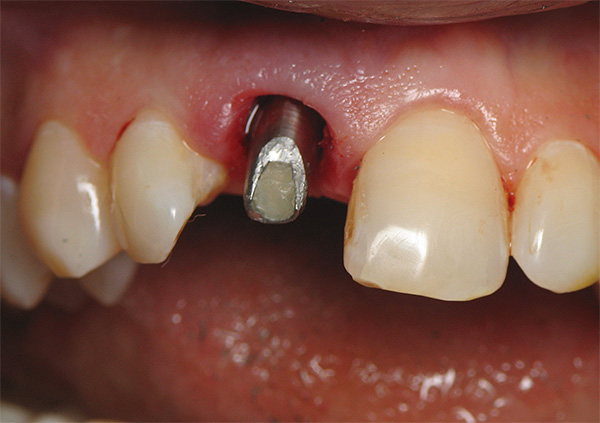

A foto abaixo mostra um exemplo de inflamação do tecido na área de um implante instalado: